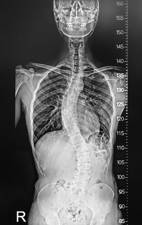

La escoliosis es una enfermedad que afecta normalmente a adolescentes y que se caracteriza por ser una deformidad tridimensional. Las vértebras se encuentran rotadas sobre su eje, cuando vemos la espalda desde el frente esta curvada y si la vemos de lado hay una variación en las curvas fisiológicas de la espalda. Para tener una escoliosis tienen que existir rotación axial y al menos 10º de curvatura.

El diagnóstico de una escoliosis del adulto se realiza mediante una simple radiografía. Utilizaremos una radiografía especial que denominamos 30×90 en la que veremos toda la columna desde la cabeza hasta la pelvis.

En esta radiografía valoraremos si la columna esta equilibrada, es decir al mirar la radiografía de frente el peso de la cabeza tienen que recaer sobre la pelvis. También miraremos la radiografía del perfil de la espalda y valoraremos si el peso de la cabeza recae sobre el sacro. Para ello lo que hacemos es trazar una línea desde el centro de la vértebra C7 y vemos a que altura de la pelvis cae. Si la línea de la vértebra C7 cae muy por delante de la pelvis tendremos una pérdida del equilibrio sagital. Pincha en este enlace si estas interesado en saber la importancia del equilibrio sagital como origen del dolor de espalda.

En la radiografía también observaremos si hay inestabilidades, espondilolistesis o desplazamientos laterales. Desplazamientos laterales superiores a 2-3 mm son causa importante de dolor.